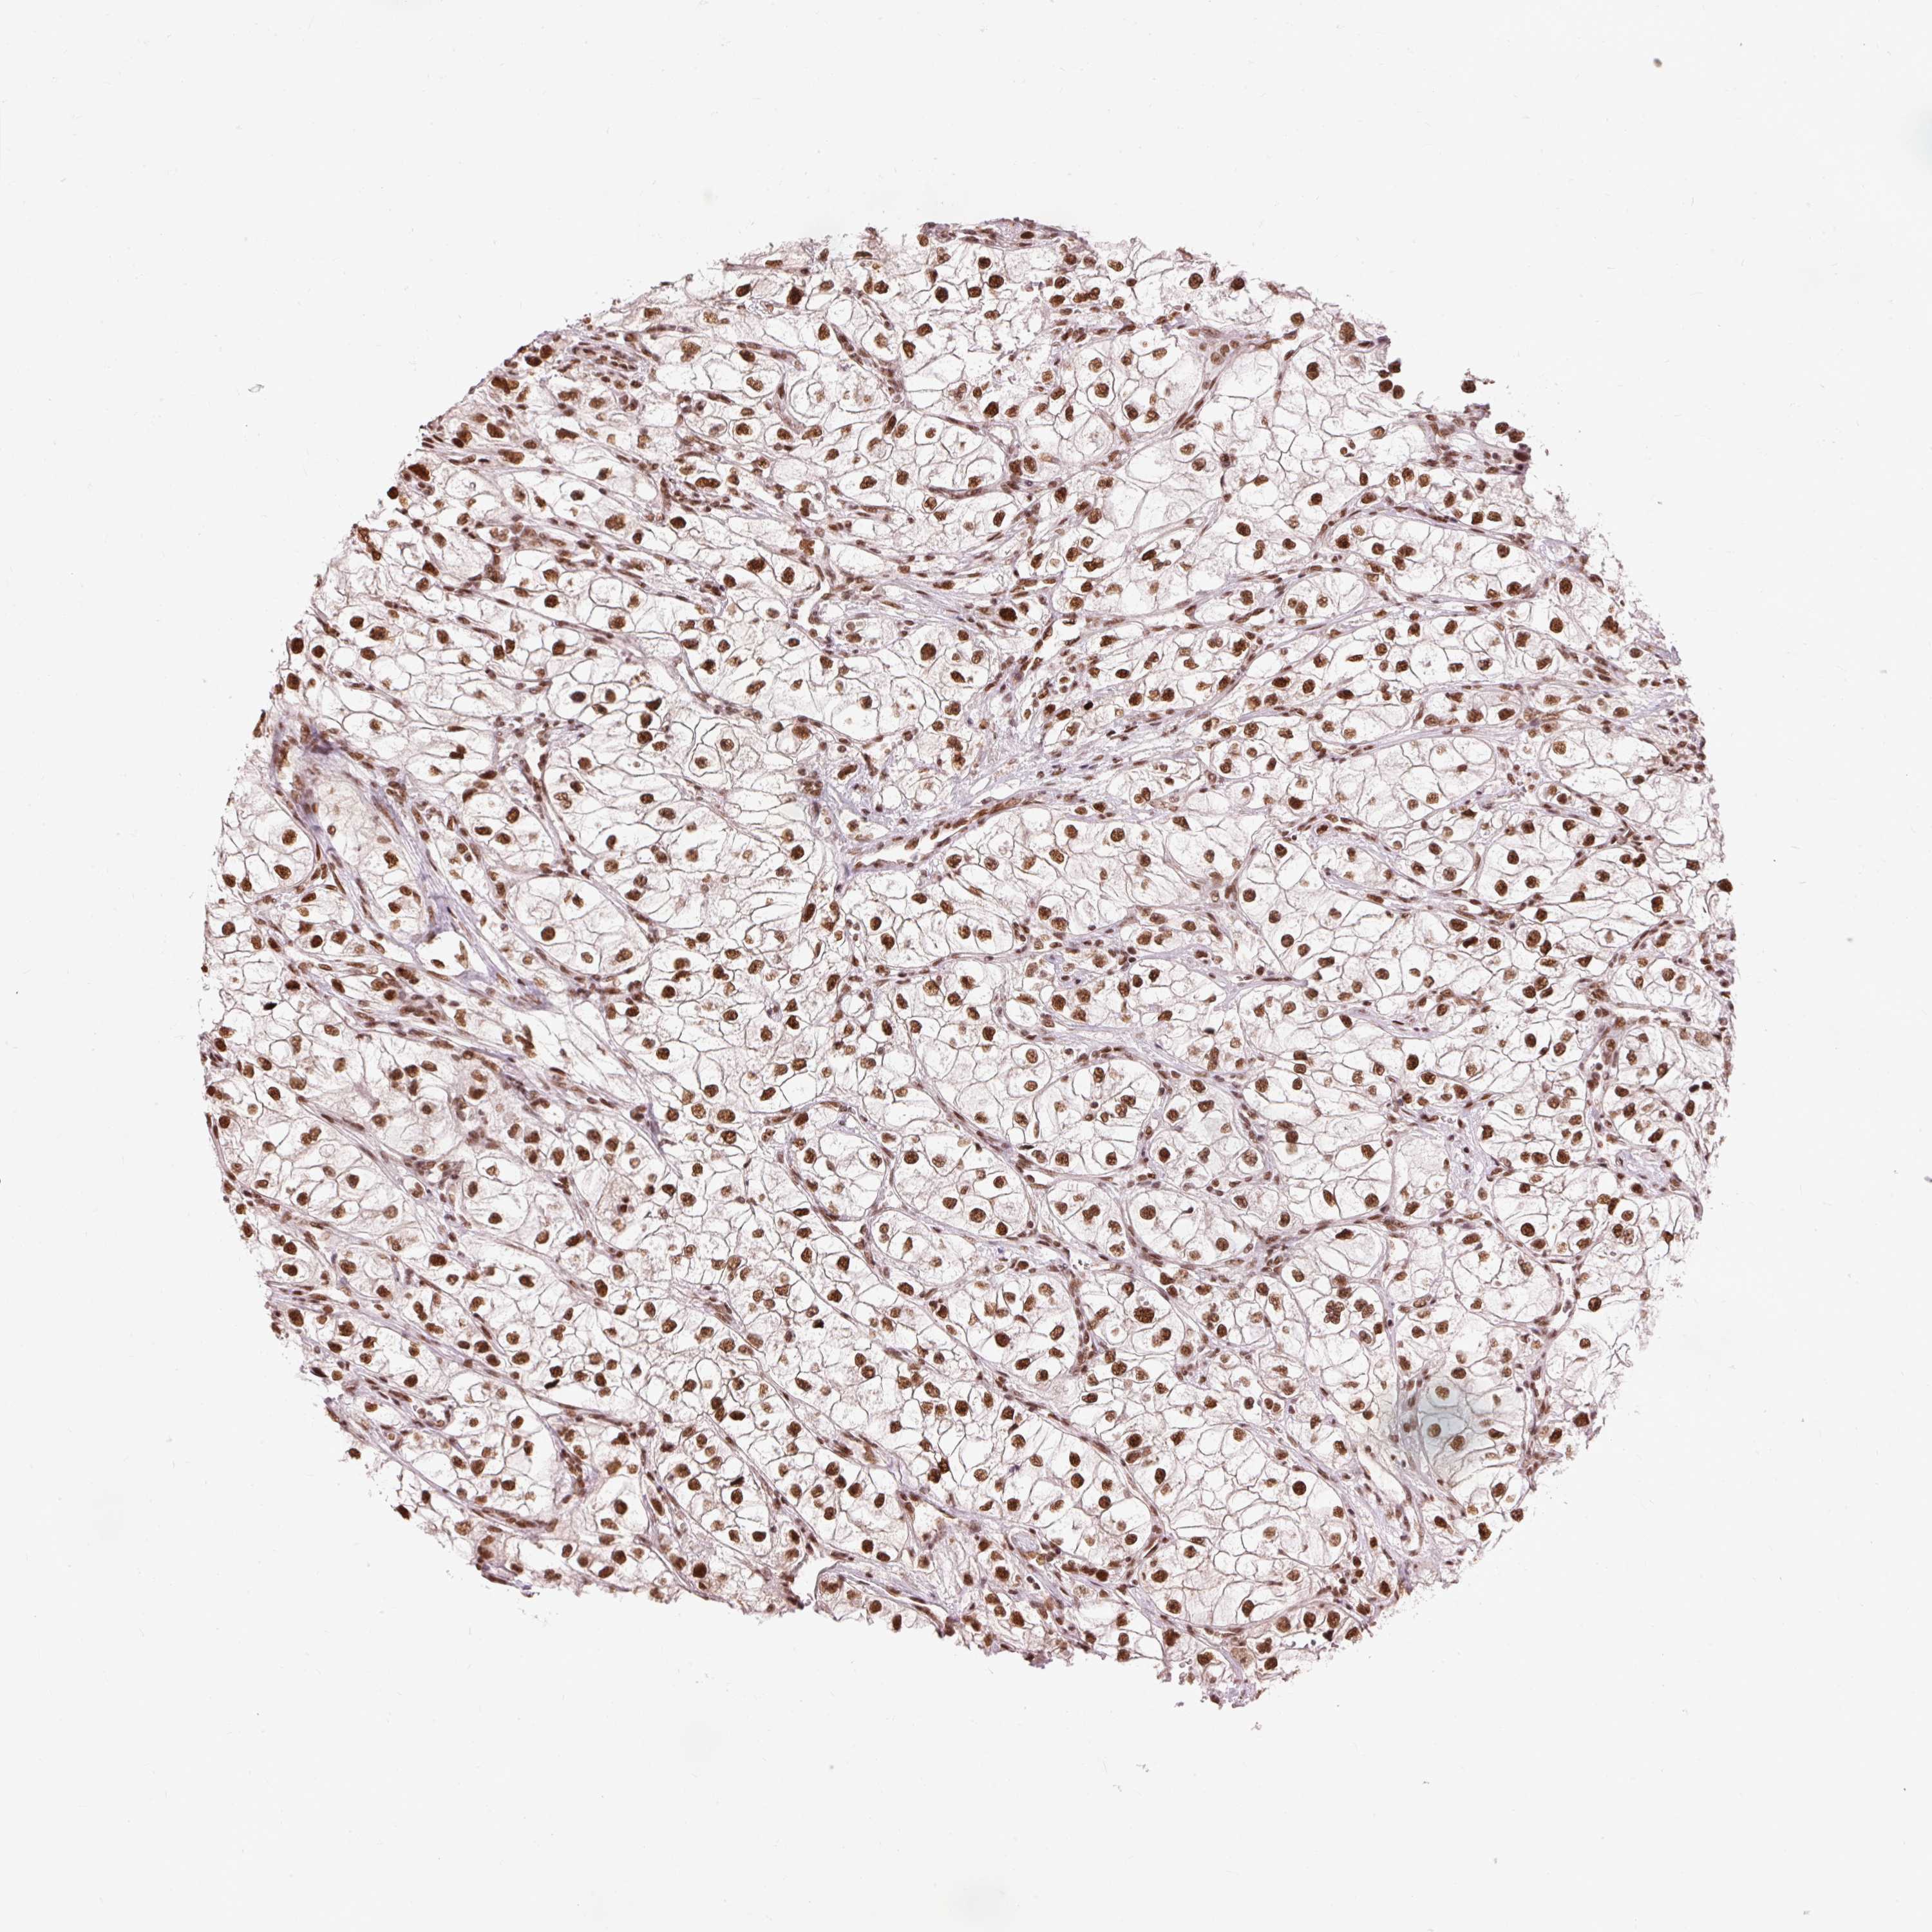

KIDNEY RENAL CLEAR CELL CARCINOMA (VALIDATION) - Interactive survival scatter ploti

The Survival Scatter plot shows the clinical status (i.e. dead or alive) for all individuals in the patient cohort, based on the same data that underlies the corresponding Kaplan-Meier plots. Patients that are alive at last time for follow-up are shown in blue and patients who have died during the study are shown in red.

The x-axis shows the expression levels (FPKM) of the investigated gene in the tumor tissue at the time of diagnosis. The y-axis shows the follow-up time after diagnosis (years). Both axes are complimented with kernel density curves demonstrating the data density over the axes. The top density plot shows the expression levels (FPKM) distribution among dead (red) and alive patients (blue). The right density plot shows the data density of the survived years of dead patients with high and low expression levels respectively, stratified using the cutoff indicated by the vertical dashed line through the Survival Scatter plot. This cutoff is automatically defined based on the FPKM cutoff that minimizes the p-score. The cutoff can be changed by dragging the vertical line or by entering a cutoff value in the square labeled "Current cut-off".

Under the Survival Scatter plot the p-score landscape (black curve; left axis) is shown together with dead median separation (red curve; right axis). Dead median separation is the difference in median mRNA expression between patients who have died with high and low expression, respectively. It is calculated as follows: median FPKM expression of dead patients with high expression - median FPKM expression of dead patients with low expression. This is intended to aid the user in visually exploring custom cutoffs and the associated p-scores and dead median separation.

Individual patient data is displayed and can be filtered by clicking on one or more of the category buttons on the top of the page. Categories describing expression level and patient information include: high, low, alive, dead, female, male and tumor stages. The scale of the x-axis can be toggled between linear and log-scale by clicking on the "x log" button. Mouse-over function shows TCGA ID, patient information and mRNA expression (FPKM) for each patient.

& Survival analysisi

Kaplan-Meier plots summarize results from analysis of correlation between mRNA expression level and patient survival. Patients were divided based on level of expression into one of the two groups "low" (under cut off) or "high" (over cut off). X-axis shows time for survival (years) and y-axis shows the probability of survival, where 1.0 corresponds to 100 percent.

ZBTB44 is validated prognostic, high expression is favorable in Kidney Renal Clear Cell Carcinoma (validation)

Best expression cut offi

Based on the FPKM value of each gene, patients were classified into two groups and association between prognosis (survival) and gene expression (FPKM) was examined. The best expression cut-off refers the FPKM value that yields maximal difference with regard to survival between the two groups at the lowest log-rank P-value. Best expression cut-off was selected based on survival analysis .

When clicking on this number, the vertical dashed line indicating cut-off, the interactive survival plot, and the Kaplan-Meier curve will be adjusted to show results based on the best expression cut-off.

: 24.27

Average pTPM 22.5

Number of samples 100